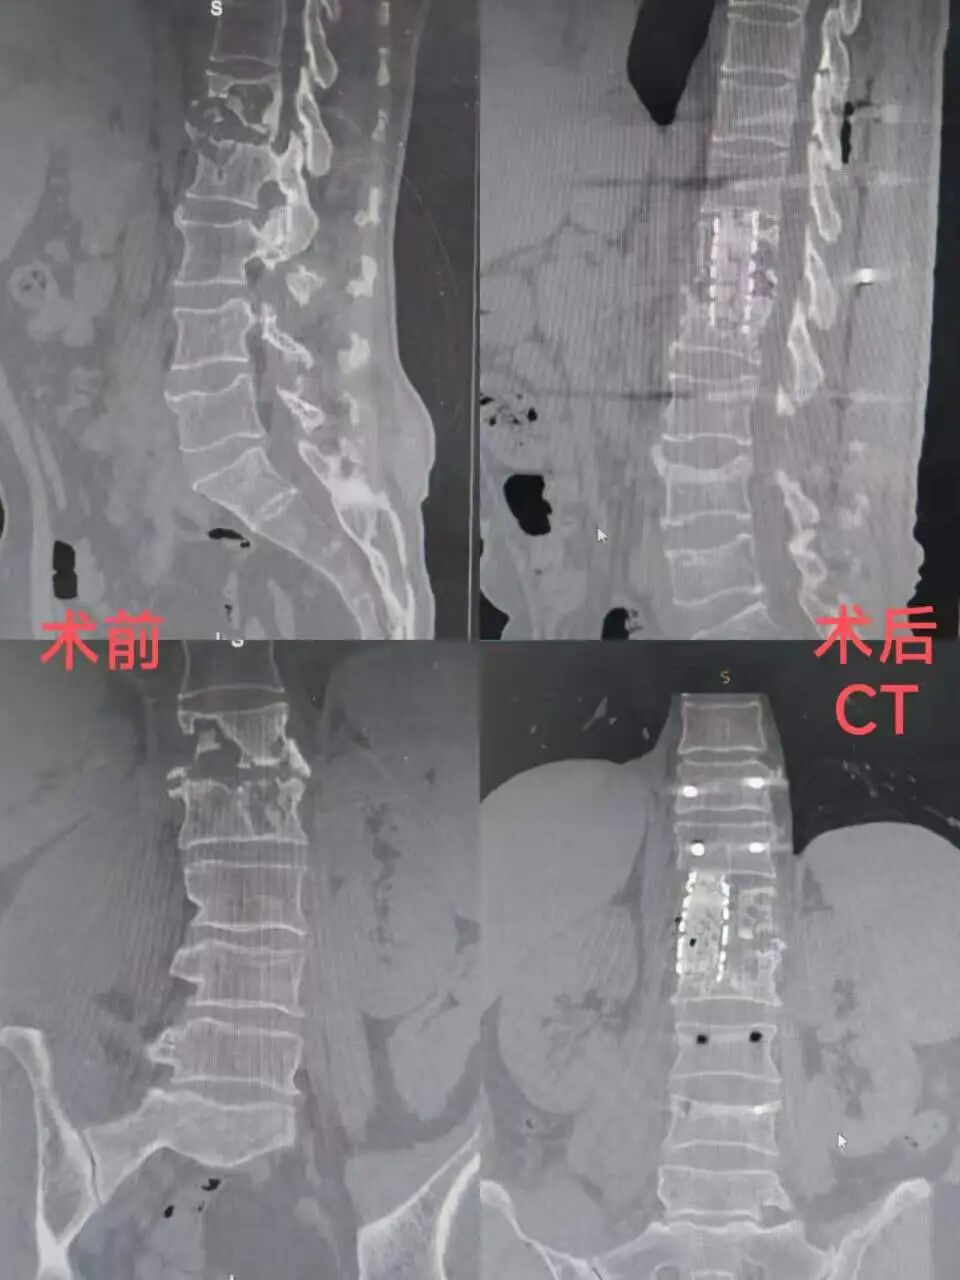

62岁的李先生因颈椎结核入院,病情复杂、治疗周期长,一家人正为后续手术费用发愁。科室第一时间评估并协助申请,基金迅速为其提供2000元专项补助。李先生家人感慨道:“在最难的时候,这笔补助真是及时雨,让我们能安心治病,也看到了希望。”